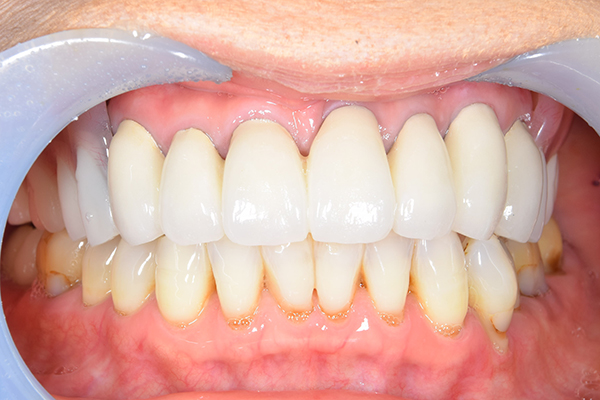

お口の中に入れた状態です。 見た目も最初とほとんど変わることなく作成できました。 維持や吸着に関しても問題ないようでした。

お口の中に入れた状態です。 非常に見た目もよい出来となりました。 バネがみえないと見栄えが全然ちがいます。